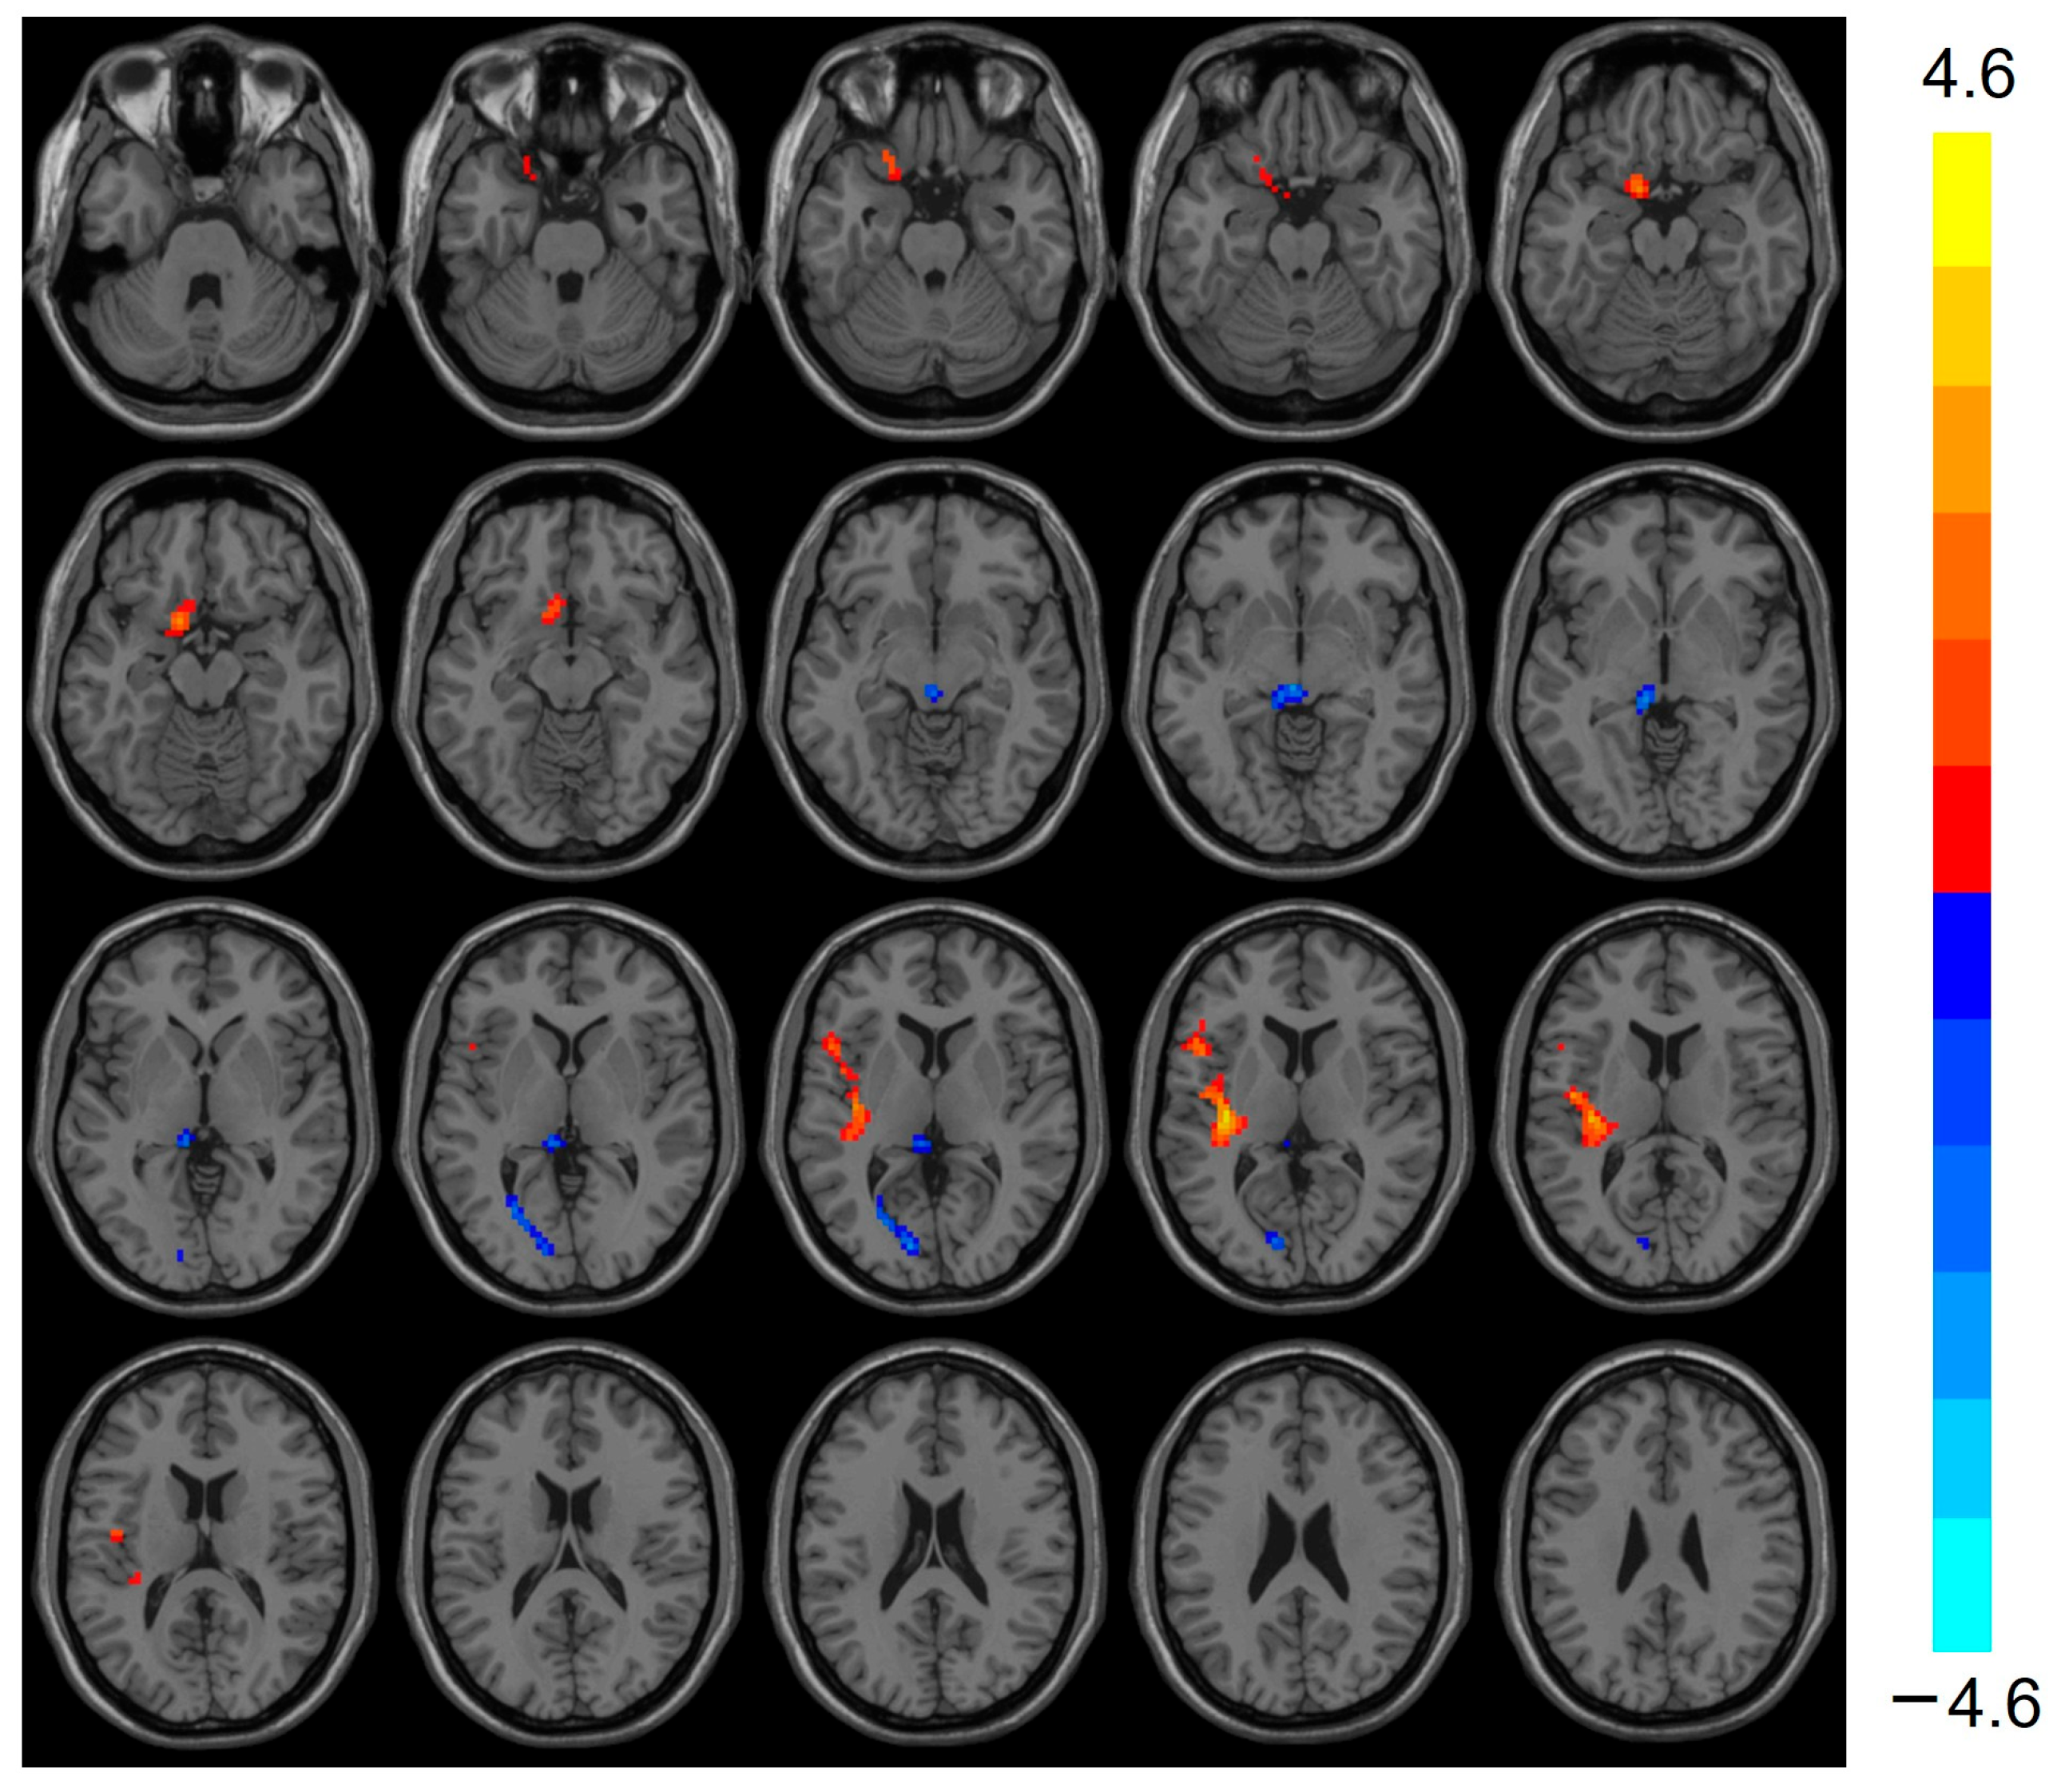

3.2. ReHo Analysis Results

| Regions | Clusters Voxels | Peak MNI Coordinate | T-Values | ||

|---|---|---|---|---|---|

| x | y | z | |||

| Frontal_Sup_R | 43 | 24 | 6 | 54 | −4.422 |

| Thalamus_L | 29 | −9 | −30 | −3 | −3.911 |

| Calcarine_L | 34 | −12 | −84 | 6 | −3.640 |

| Temporal_Sup_L | 26 | −36 | −21 | 9 | 4.609 |